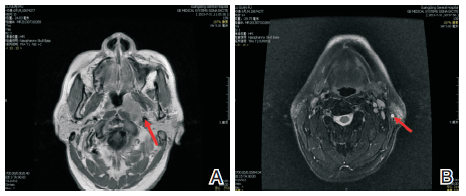

鼻咽+颈部MRI(2013-07-31)示:(1) 鼻咽左侧壁可见一椭圆形软组织肿块影, 最大径约31 mm× 19 mm, 肿块累及头长肌、腭帆提肌、腭帆张肌、翼突。左侧咽隐窝及咽鼓管咽口变窄、消失, 右侧咽隐窝及咽鼓管清晰。双侧颈部Ⅱ 、Ⅲ 区见多发小淋巴结, 最大者约8 mm× 10 mm。诊断:鼻咽左侧壁肿块, 考虑鼻咽癌并累及头长肌、腭帆提肌、腭帆张肌、翼突(见图1)。

图1 鼻咽颈部MRI图像(2013-07-31)